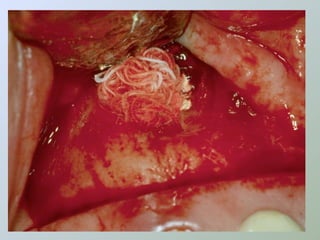

Paraendodôntica uepg